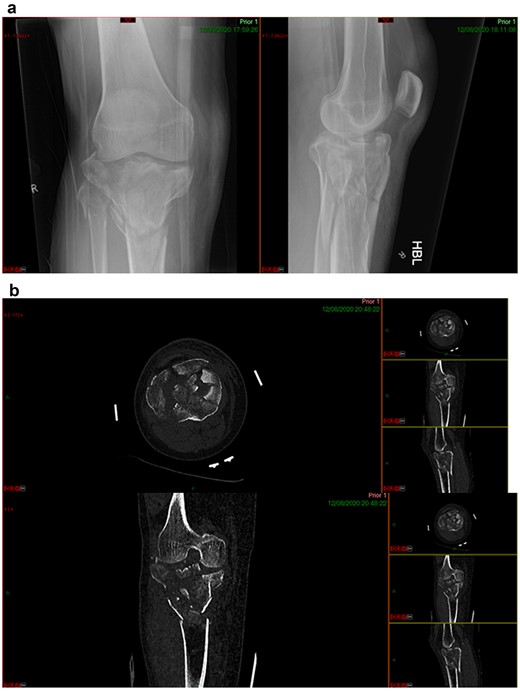

A 68-year-old gentleman who was diagnosed with a Schatzker type VI fracture having fallen 3 m from a ladder (Figs 1 and 2). The injury was closed and neurovascularly intact. The patient was monitored for signs of compartment syndrome. He rapidly developed significant fracture blisters that persisted for over 2 weeks despite regular dressing care. He was deemed too high risk for acute operative intervention because of a high risk of wound complications. Following a multidisciplinary team discussion, he was managed in a cast then a knee brace, mobilising non weight bearing for 12 weeks, at which point the fracture was seen to be healing in a valgus malalignment. The patient was allowed to partially weight bear and received physiotherapy. He was reviewed regularly until fracture had united (Fig. 3). At 8 months post-injury, the patient underwent total knee arthroplasty utilizing a Depuy Synthes (Warsaw, In) PFC Sigma TC3 tibial metaphyseal sleeve and stem, and femoral component without sleeve or stem (Fig. 4). The patient was reviewed post-operatively in clinic at 6 months, the wound had fully healed and the range of motion was 0°–120°. The patient’s pain was significantly reduced, and they were independently mobile. They were kept under annual review and seen at 5 years post-operatively with an Oxford Knee score of 35; the patient used no walking aids and was pain free at rest or during normal walking, with the radiograph demonstrating good osseointegration. The latest follow-up at 8 years revealed no radiographical change in implant (Fig. 5).